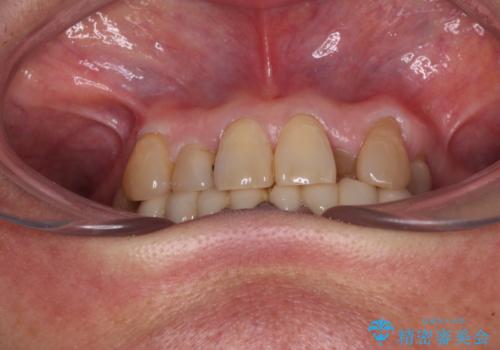

- 常に外れている下顎のブリッジと、前歯のデコボコと色を気にして来院された患者様です。

前歯のデコボコおよび奥歯の咬み合わせを改善するために、上顎左右の小臼歯を欠損スペースを利用して歯列を整え、矯正治療後に気になる上下前歯などをオールセラミッククラウンで美しく仕上げていくこととしました。